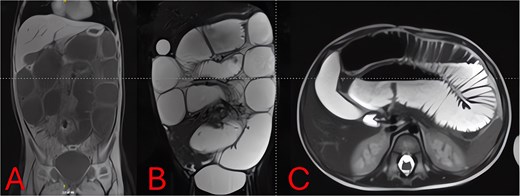

Urgent diagnostic laparoscopy was converted to a minilaparotomy for better visualization. Markedly distended loops were exteriorized (Fig. 4A). Dense inflammatory adhesions tethered the distal ileum to a perforated appendix with a fecolith, creating a fixed kink. Appendectomy with base transfixation, adhesiolysis, repair of a small jejunal serosal tear, and peritoneal lavage were performed (Fig. 4B). A Foley catheter and nasogastric tube were left in situ for 24 and 72 hours, respectively.

Intraoperative findings and resolution. (A) Intraoperative photo of markedly distended, congested small-bowel loops exteriorized at laparotomy. (B) Intraoperative view of the perforated appendix and surrounding abscess/adhesions tethering the distal ileum, causing mechanical obstruction.

Laparoscopic appendectomy is generally favored for uncomplicated appendicitis, but dense adhesions or perforation may necessitate conversion to open surgery for adequate exposure and sepsis control [8]. In this case, a supraumbilical laparotomy was required due to massive bowel dilation and limited visualization. Intraoperative findings confirmed a perforated appendix with dense phlegmon and adhesions, prompting adhesiolysis, appendectomy, and peritoneal lavage (Fig. 4). Timely surgical intervention and targeted antibiotic therapy typically yield favorable outcomes in pediatric SBO due to appendicitis. Our regimen of meropenem followed by gentamicin for ESBL-producing E. coli, combined with early operation, led to rapid CRP decline and an uneventful recovery [9].